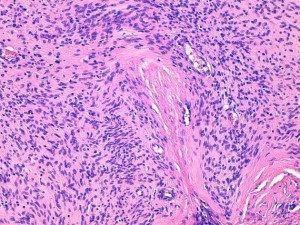

- La nécrose doit être différenciée des remaniements mucineux, hyalins, hémorragiques ou traumatisés par la chirurgie ou la technique biopsique (Fig 2)

- Si un type histologique est reconnu, il s’agit soit d’un score 1 (bien différencié) (Fig 3,6,8,11) soit d’un score 2 (peu différencié) (Fig 4,7,9,12). Les tumeurs bien différenciées sont celles qui ressemblent le plus au tissu mésenchymateux adulte mature (Fig 3,6,8,11). Au contraire, les tumeurs peu différenciées ont peu de ressemblance avec le tissu mésenchymateux mature normal, même si elles peuvent être d’un type histologique particulier. Si le type d’une tumeur ne peut être établi ou si l’architecture de la tumeur est difficile à identifier, il s’agira d’une tumeur indifférenciée par définition et de score 3 (Fig 5,10). Les auteurs insistent sur le fait que le score de différenciation n’a rien à voir avec une histogenèse incertaine (ainsi si les tumeurs péri-vasculaires ou les PNSTs ont une histogenèse encore controversée, mais elles ressemblent néanmoins à un tissu mésenchymateux mature normal et ne doivent pas systématiquement se voir attribuer le score de 3 si leur architecture typique est correctement identifiable).